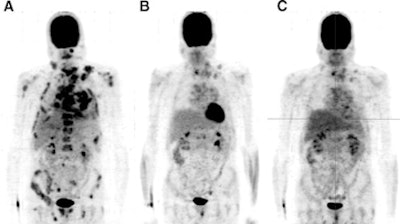

| FDG-PET scans of a 43-year-old man with metastasized medullary thyroid cancer before (A) and at 12 (B) and 24 (C) weeks after start of treatment with 300 mg of vandetanib per day. Image courtesy of the Journal of Nuclear Medicine. |

Results showed that glucose levels were within the reference range at each scanning time point. The maximum standardized uptake value (SUV) was measured in 10 reference lesions at the baseline scan and at each follow-up scan. The SUV dropped from 8.1 ± 1.5 at baseline to 4.0 ± 1.3 after 12 weeks and 3.4 ± 1.2 after 24 weeks of treatment.